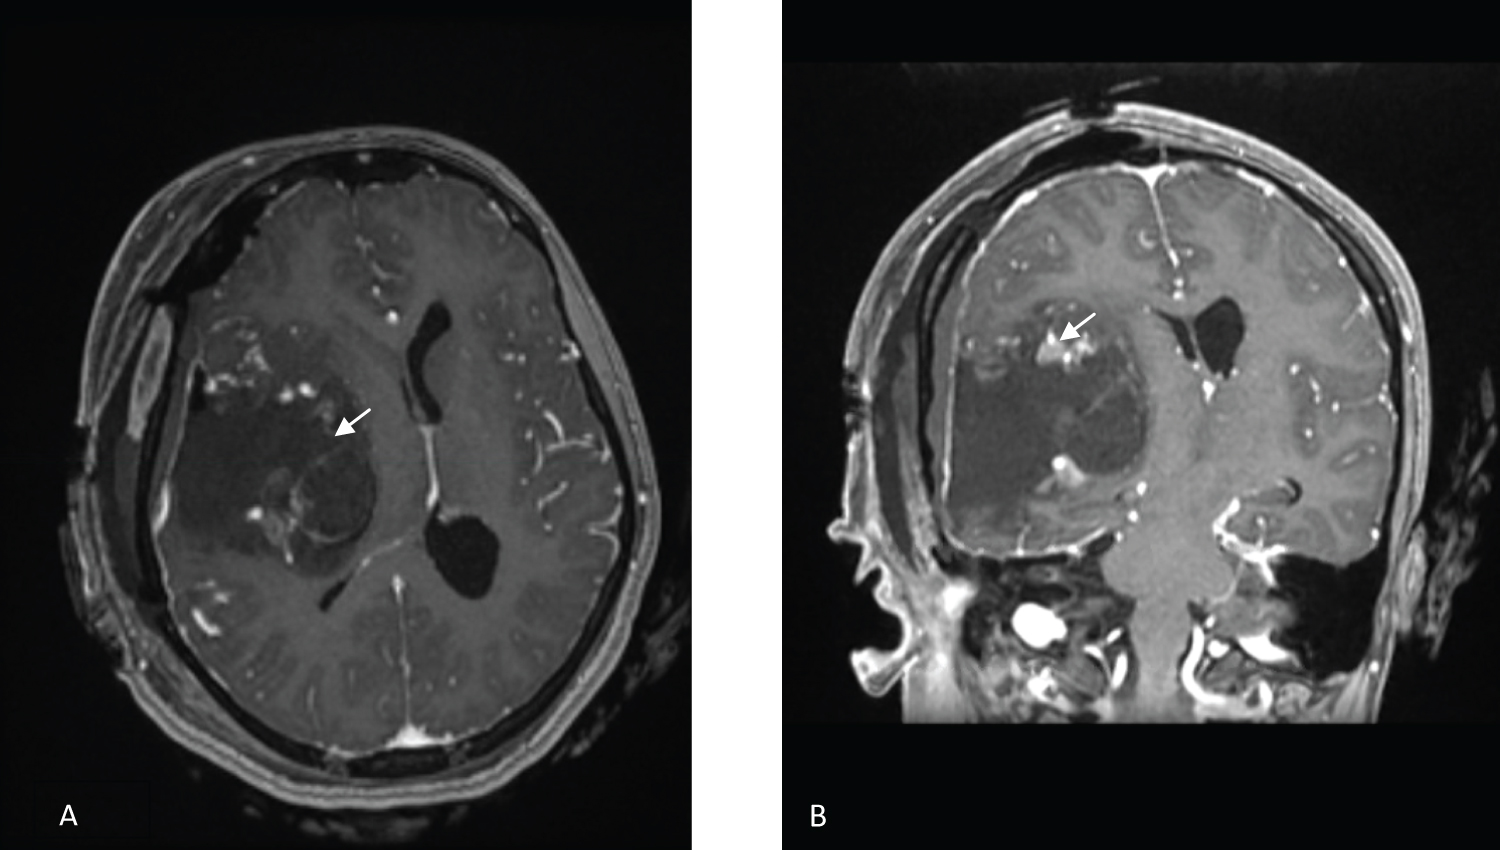

MRI of the brain (Figure 1) showed a mass measuring 5.1*5.6*5.4 cm in the anteroposterior, transverse, and craniocaudal dimensions. The mass was heterogeneous, showing moderate enhancement and a few foci of calcification and hemorrhage. The lesion was centered in the right Sylvian cistern, invading the insula and right frontal and temporal lobes. The mass abutted the dura, without a dural tail. Multiple enlarged blood vessels were seen coursing through the mass. There were large arterial feeders from the dilated right MCA and draining veins leading to a dilated right superficial middle cerebral vein. MR perfusion demonstrated markedly raised perfusion seen within the mass.

Figure 1: Axial, coronal, and sagittal views (A,B,C) of contrast-enhanced T1 MRI. Axial view (D) of a T2 MRI sequence showing a right frontotemporal tumor (Arrows) with a significant mass effect and foci of hemorrhage and calcification. View Figure 1